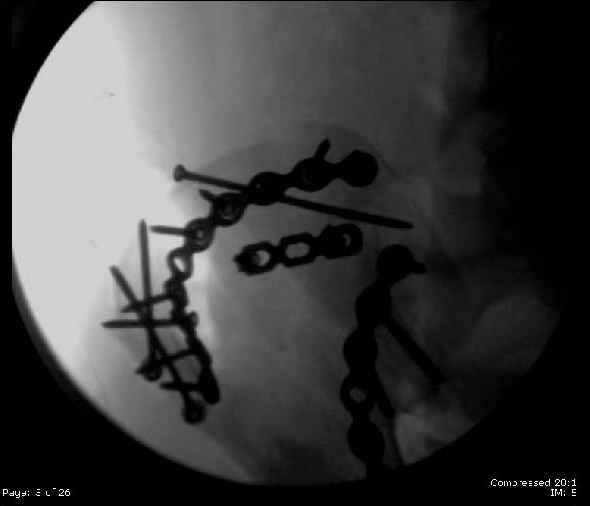

Here are the postop fluoros.

First exposed symphysis & clamped w/Faraboeuf as close to anatomic as possible.

Then extended to R ilioinguinal,really just the lateral window.

Reduced the triangular wedge piece of iliac wing to posterior intact ilium (crescent), held w/k-wire, then used 3-hole push plate to keep from moving, lagged from lat-med w 3.5 screw.

Then 6-hole plate along brim with 1 screw in R sacral ala. Then lagged 2 screws along crest A --> P. finally 10-hole plate along inner aspect of crest. R posterior ilium still a bit stepped off.

Symphysis then 'fine-tuned' & reduced as close as possible to anatomic (but, still with forward rotation of R hemipelvis - or, is it extension?) Accepted that amount of deformity and plated symph

with 4-hole symphyseal plate.

Fluoroed L SI joint and it seemed stable, but wide. So, applied c-clamp to try to squeeze down L SI joint (and note, on the last slide attached, that it's still wide), and got it closer. Single perc Iliosacral screw 40mm thread.

Applied second plate anteriorly on symphysis as I wasn't confident L SI was as stable as it could be and wanted to protect it better.

Thoughts? Thanks for the advice, it's appreciated.

Jeff